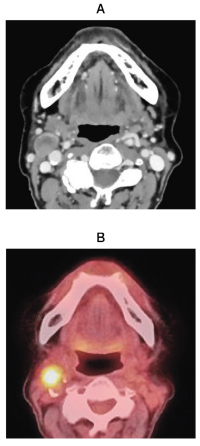

歯肉癌の転移リンパ節の造影CT、FDG-PET/CT及びドプラ超音波横断像を別に示す。転移リンパ節の部位はどれか。1つ選べ。

a. 頰リンパ節

b. 咽頭後リンパ節

c. 鎖骨上窩リンパ節

d. オトガイ下リンパ節

e. 上内頸静脈<上内深頸>リンパ節